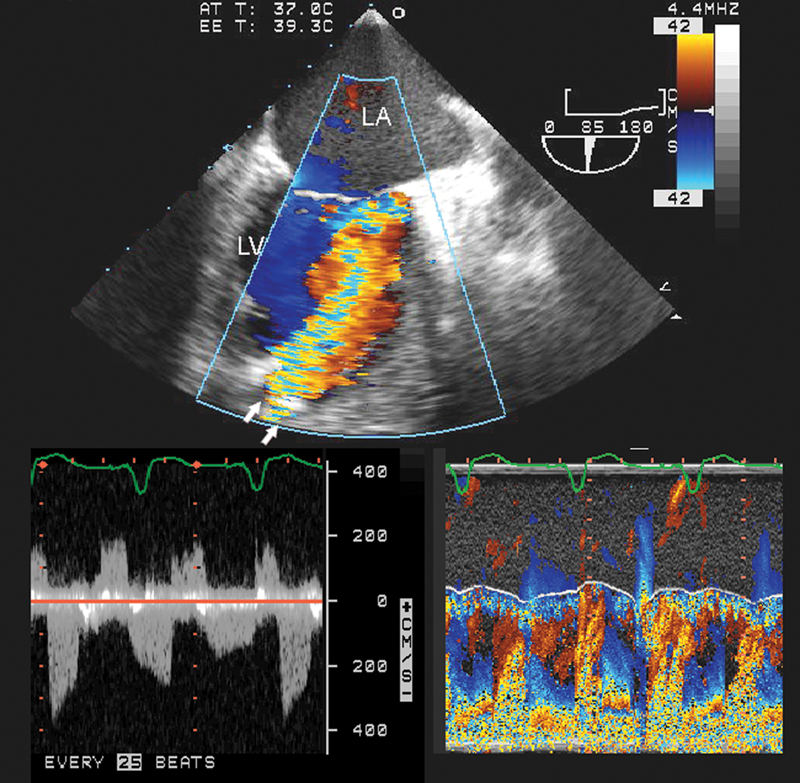

فحوصات تشخيصية لبعض امراض القلب والشرايين التاجية